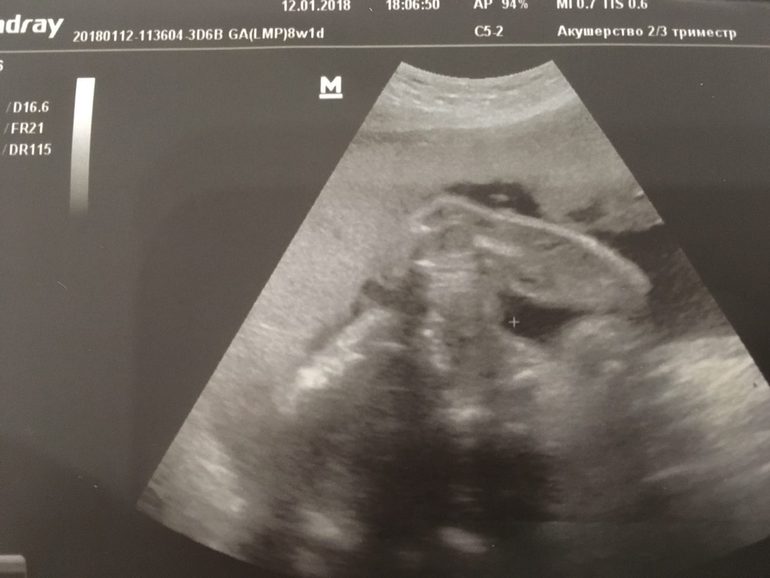

И вот вчера (24-25 неделя) была у своего доктора, и она сказала, что "похоже на девочку":

Только через неделю иду на 3D, где уже точно надеюсь скажут:)

Девчонки, а вы что-то понимаете в этих снимках?) На кого оно больше похоже?)